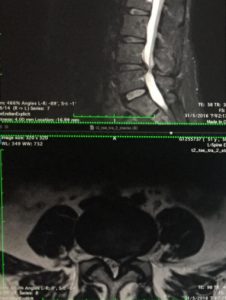

After the minimally invasive surgery of the herniated disc, the doctor advised that she should completely avoid lifting heavy objects, not doing exercises or bending after the operation. Unfortunately, the patient did not comply. Three weeks after the operation, Ms. Li’s lumbar disc herniated again in the 4th and 5th lumbar vertebrae (see Figure 3), so that the legs and buttocks are painful and numb. The patient did not want to have another operation in a short time, and the condition was not serious, so she accepted the Cox® decompression manipulation. After 30 times of Cox® decompression manipulation for four months, the pain and numbness of the patient’s legs and buttocks disappeared. The MRI comparison showed that the re-protruding disc after the operation was significantly reduced and reabsorbed, and the previous compression of the nerve was also improved (see Figure 4). The patient now maintains monthly Cox® decompression manipulation to maintain the disc condition.